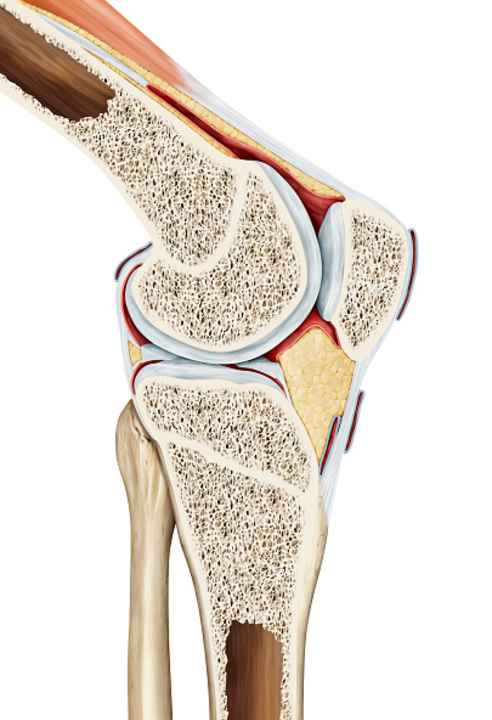

Gesundes Knorpelgewebe ist nicht von Blutgefäßen durchzogen, sondern muss durch die Gelenkflüssigkeit mit Nährstoffen versorgt werden. Wer regelmäßig in die Pedale tritt, sorgt also für die Ernährung und damit Gesundhaltung seines Knies. Bewegt sich das Gelenk gleichmäßig auf einer festgelegten Kreisbahn, wird das Knie weniger durch Verdreh-Bewegungen belastet, als bei anderen Bewegungen. Ein Knie besteht jedoch nicht nur aus Knorpel, sondern ist ein hochkomplexes “Bauteil” des Körpers. Auch ist Radfahren nicht gleich Radfahren. Für die Knie ist es ein gewaltiger Unterschied, ob sie auf einem Ergometer gleichmäßig durchbewegt werden oder auf einem Mountainbike durchs Gelände poltern.

Verletzungen durch Stürze sind geschwindigkeitsabhängig und können zum Beispiel auch komplexe Knochenfrakturen sein. Ein weiteres Problem beim Sturz aufs Knie ist das Gewicht. Auffällig ist seit der Verbreitung von E-MTBs die Zunahme an Tibiakopf-Frakturen (Bruch des Schienbeinkopfes, Anm. d. Redaktion). Diese sind für das Kniegelenk relativ heftig, weil sie oft mit einer Verletzung von Bändern und Kapseln in Verbindung stehen. Bei einem schwereren Bike kommt es natürlich zu höheren Kräften. Bezieht man das meist höhere Tempo von E-Bikes mit ein, steigt die Belastung exponentiell.

Prinzipiell sollte es im Reha-Prozess das Ziel sein so viel, wie möglich an Beweglichkeit wiederzuerlangen. Bei einer schweren Verletzung, wie einer Tibiakopf-Fraktur ist das nicht immer einfach. Das ist kein angefahrener Kotflügel mehr, sondern eine starke Beeinträchtigung der statischen Situation und der Gelenkmechanik im Knie. Wer eine Verletzung hat, sollte unbedingt versuchen den Bewegungsbereich des Gelenks so lange wie möglich zu erhalten. Bei einem Streckdefizit von fünf Grad beispielsweise darf sich dieses nicht schleichend auf zehn oder sogar 15 Grad erhöhen. Der Körper reagiert dann nämlich mit Ausgleichsbewegungen in der Hüfte oder im Becken und Bewegungsabläufe werden nicht mehr funktionell sauber ausgeführt, was dann Probleme in anderen Körperpartien indiziert.